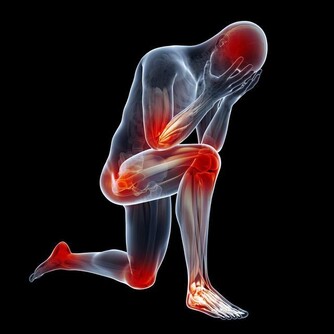

缺乏睡眠的人會出現注意力下降、認知功能障礙、記憶缺失等神經系統的改變,而神經——內分泌系統——免疫調節系統是一張相互連接、彼此影響的關係網,睡眠對神經系統的影響必定會在免疫系統上有所反映。